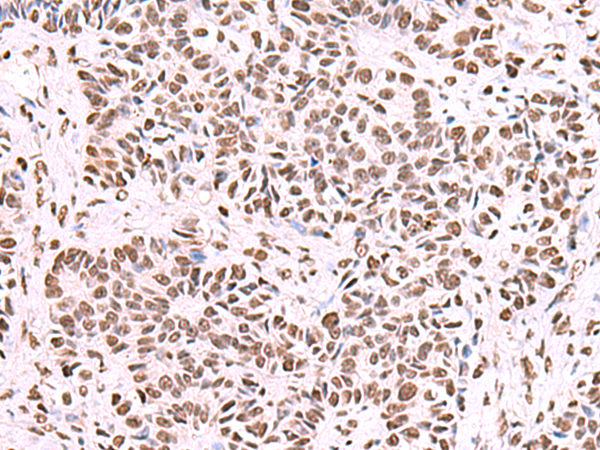

分类: 科研抗体货号: P10169别名: HMDRA1; FLB7527; PRO1999应用: WB,IHC反应种属: Human, Mouse, Rat